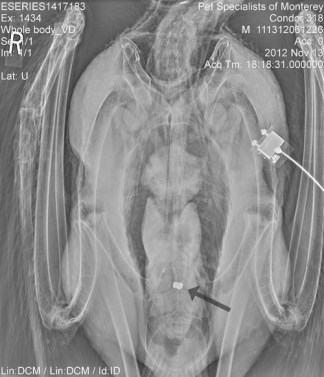

Condor 318. (Photo: Ventana Wildlife Society)

A 10 year-old male condor (#318) died after ingesting a bullet, presumably while feeding on a carcass. He was found barely alive and unable to feed or use his legs to stand. Veterinarians could not save him. A necropsy determined the cause of death was lead toxicosis. A radiograph showed multiple metal fragments and a 22 caliber lead bullet in his digestive tract.